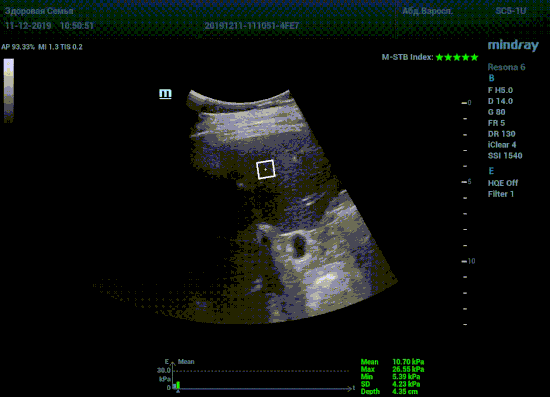

Определение плотности печени. Не ошибся ли оператор при измерении эластических свойств печени? Для оценки критериев качества предусмотрен индекс MBT, который покажет насколько «твердой» была рука оператора и двигалась ли печень. При MBT 5* рука тверда и показатели достоверны. Для оценки качества результатов используется IQR индекс, отображающий колебания показателей в точке измерения при расчете медианы. Показатели при IQR <30% считаются приемлемыми. Техника сканирования через межреберные промежутки требует размещение окна интереса на несколько сантиметром ниже капсулы, для исключения эффекта реверберации. Установка ROI на паренхиму без захвата сосудов, для исключения погрешностей измерения.

Стадия фиброза определяется по системе METAVIR Staging, построенной на данных биопсии и сопоставлении с данными эластографии. Своевременная диагностика фиброза, и начало его лечения, залог благоприятного исхода заболевания.